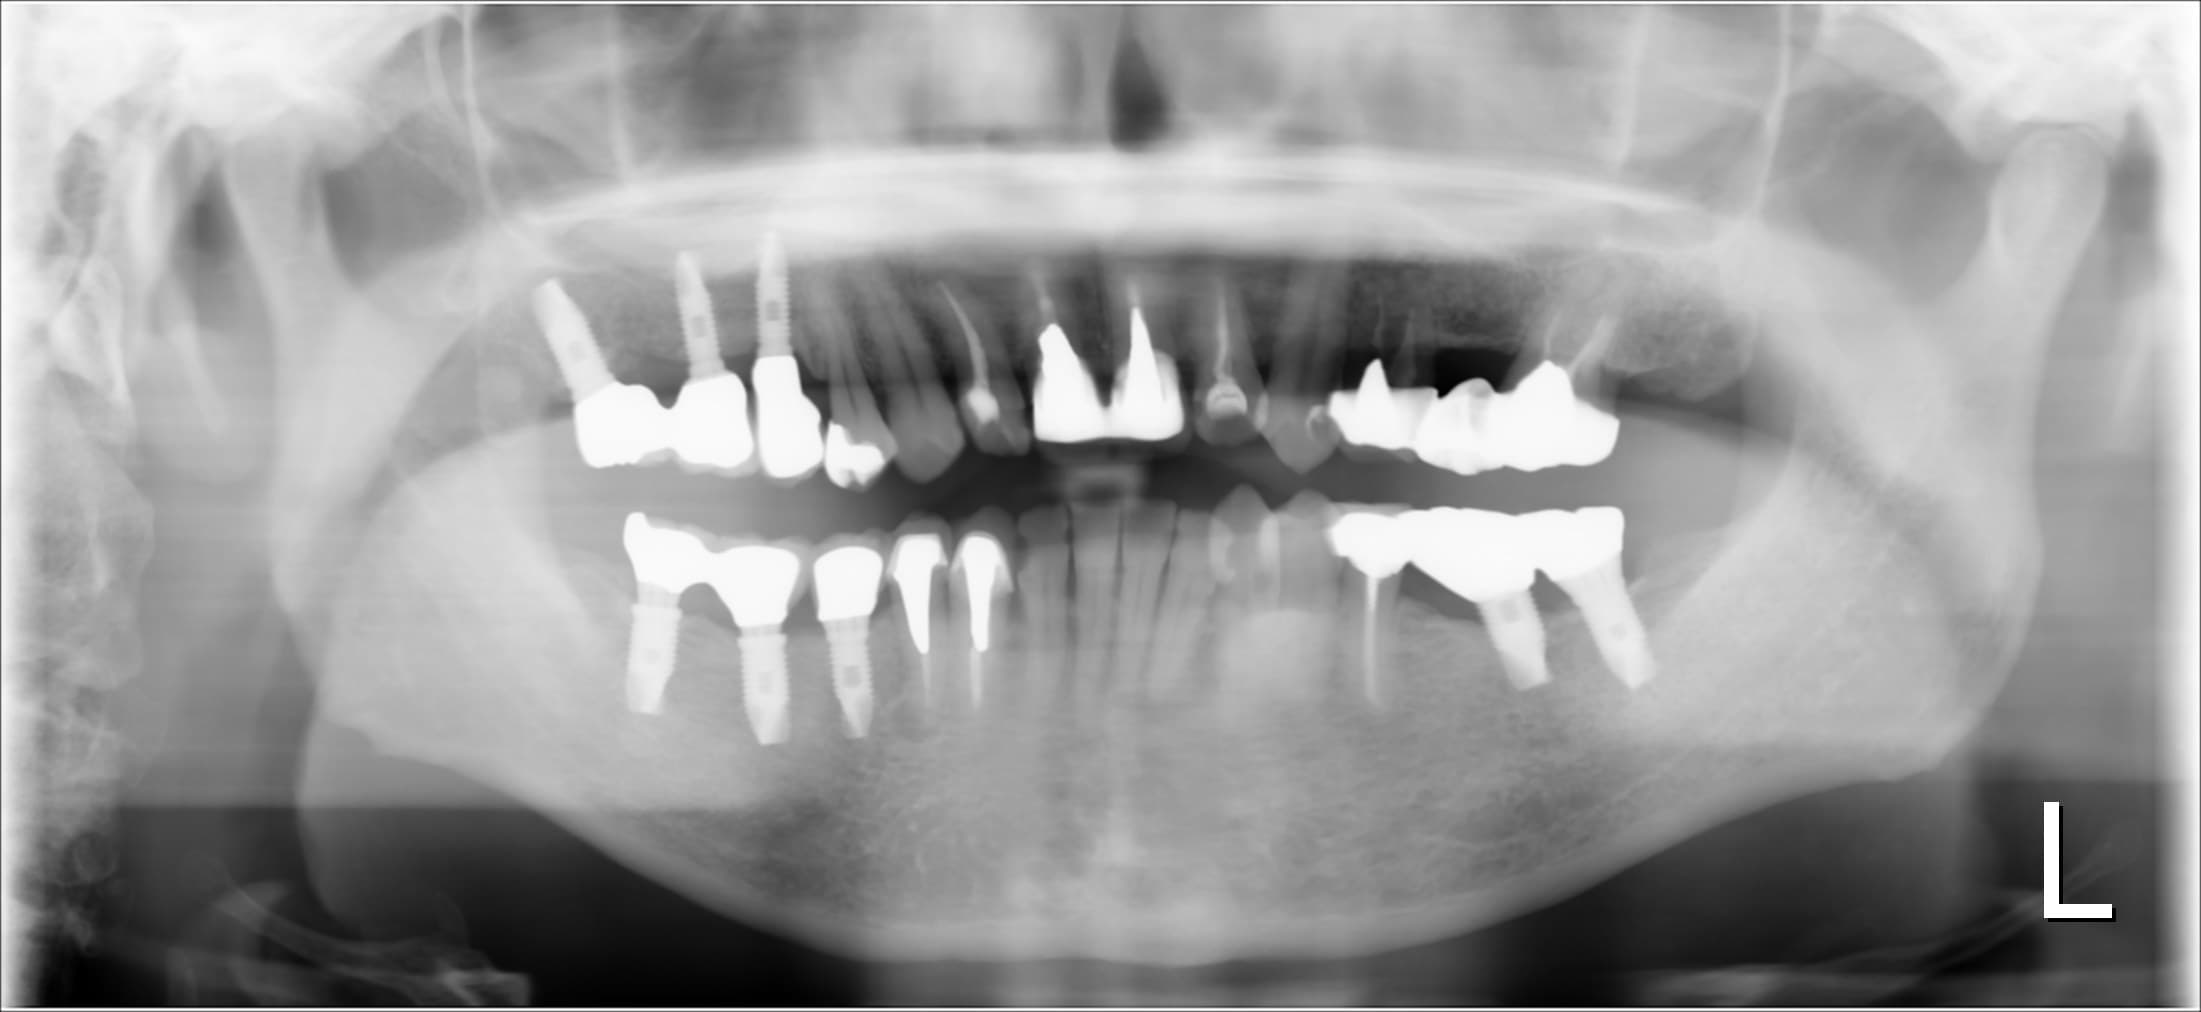

(初診時のレントゲン)

奥歯にインプラントを行っていることから、徹底した炎症のコントロールが必要ですが、残念ながら歯周病に感染しており、芳しくない事実をお伝えし、その改善のため、歯周専門治療を受けて頂く事になりました。